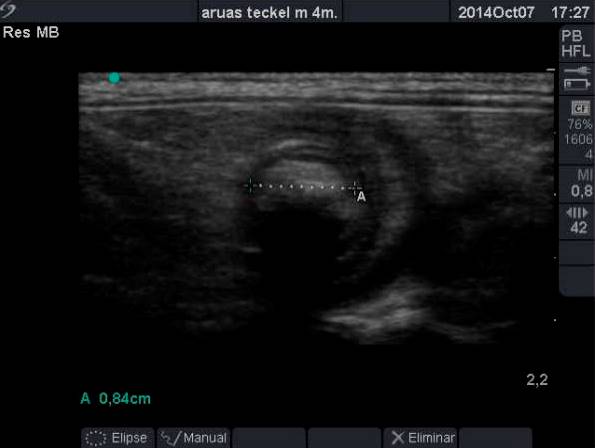

- Asa Yeyunal cráneo medial a riñón derecho (con paciente en decúbito lateral), con presencia de contenido hipoecogénico que produce sombra acústica limpia, dicha imagen es compatible con posible cuerpo extraño ecovisible de 0,84 cm de diámetro (además asa interior distendida con aumento de contenido de patrón líquido). Además se observa la presencia de múltiples capas intestinales que es compatible con posible invaginación o pseudoinvaginación intestinal, que hace que la imagen previamente descrita además de compatible con posible cuerpo extraño lo sea también con introducción de grasa abdominal.